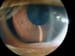

Sequelae of chronic anterior uveitis. Note the posterior synechiae (weblike attachments of the pupillary margin to the anterior lens capsule) of the right eye secondary to chronic anterior uveitis. This patient has a positive antinuclear antibodies (ANAs) and initially had a pauciarticular course of her arthritis. She now has polyarticular involvement but no active uveitis. Image courtesy of Carlos A. Gonzales, MD.